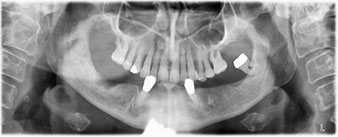

The 64-year-old patient presented with residual dentition of teeth 38, 33 and 43 and a clasp denture in the mandible (Fig. 1 and 2).

Fig. 1

Fig. 2